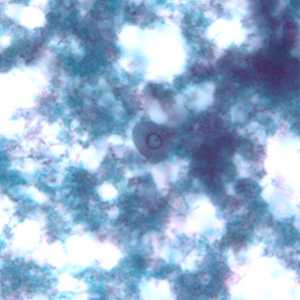

Figure A: Cysts of E. nana stained with trichrome.

Figure B: Cyst of E. nana stained with trichrome.

Figure C: Cyst of E. nana stained with trichrome.

Figure D: Cyst of E. nana stained with trichrome.